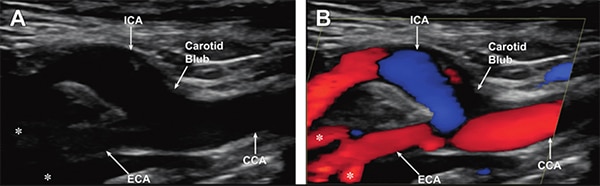

Bemærk, at der findes forskellige typer af ultralydsbilleder som vist i (Figur 2):

- Gråskala giver et grundlæggende sort/hvidt billede. Den kan opløse artefakter så små som en millimeter (mm).

- Doppler-tilstande registrerer hastigheden af et objekt i bevægelse ved at spore frekvensforskydningen af retursignalet og vise det i falsk farve. Det bruges til at undersøge blod eller andre væsker, der flyder i kroppen. Doppler-mode kræver, at man sender en kontinuerlig bølge ind i kroppen og producerer en hurtig Fourier-transformation (FFT) af retursignalet.

Figur 2: Gråskala (A) og farvedoppler (B) af de ekstrakranielle halspulsårer på niveau med halspulsårernes bifurkation. Bemærk, at forgreningerne af ECA (asterisk, nederst til venstre på hvert billede) ses bedst på farvedopplerbilleder. (CCA: common carotid artery; ICA: internal carotid artery; and ECA: external carotid artery (ECA). (Billedkilde: Radiologic Clinics of North America)

- Venøse og arterielle tilstande bruger Doppler sammen med gråskala-tilstanden. De bruges til at vise arteriel og venøs blodgennemstrømning i detaljer.